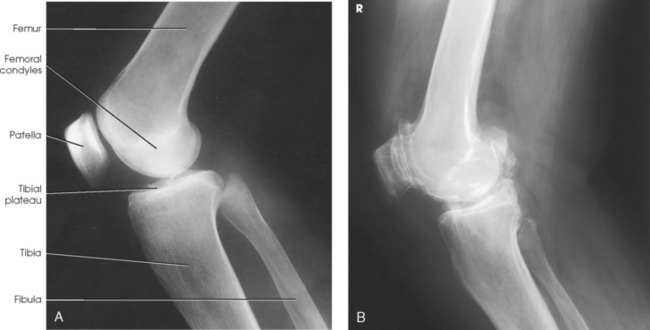

Structures shown: The resulting radiograph shows a lateral image of the distal end of the femur, patella, knee joint, proximal ends of the tibia and fibula, and adjacent soft tissue (Fig. 6-126).

Structures shown: The resulting image shows an AP projection of the knee structures (Fig. 6-121).

Structures shown: The resulting image shows a PA projection of the knee (Fig. 6-123).